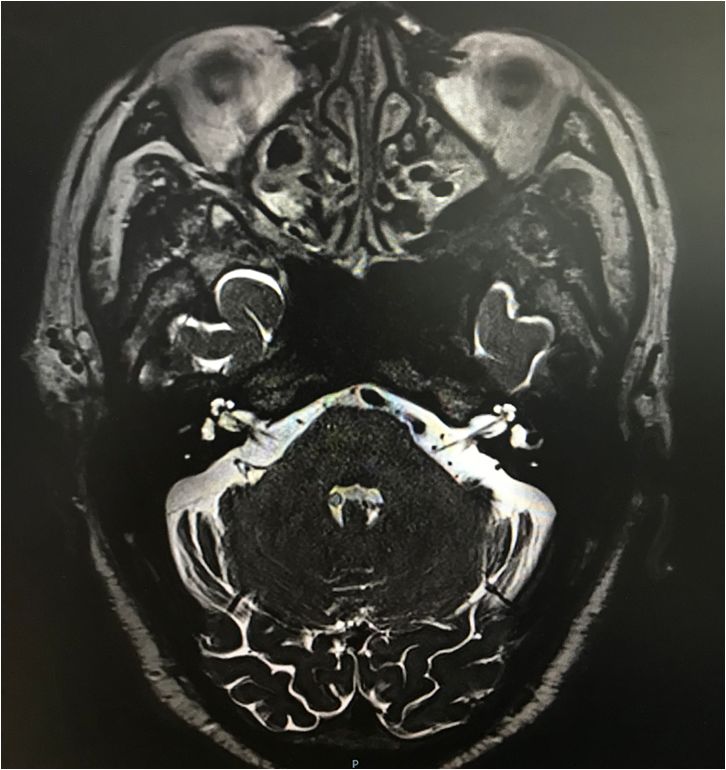

我院mr三叉神经薄层扫描提示:患者左侧三叉神经颅内段内侧缘小血管骑

图片尺寸764x622